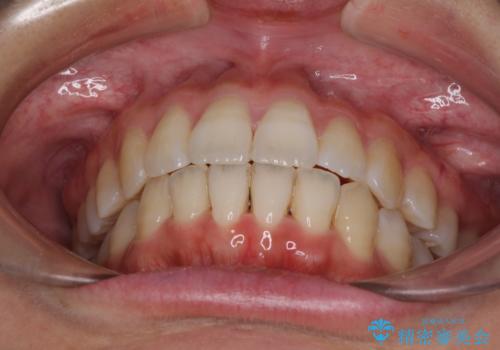

歯列全体の拡大と、歯と歯の間を削ることでスペースを獲得し、インビザラインによる矯正治療を行うこととしました。

骨格的な問題を抱えた左奥以外は比較的早く咬み合わせが改善しましたが、左奥はどこで咬み合えば良いのか分からず、大変不便な思いをされていました。

ゴムかけにご協力いただき、最終的には反対咬合を改善することができ、患者様には大変満足していただきました。